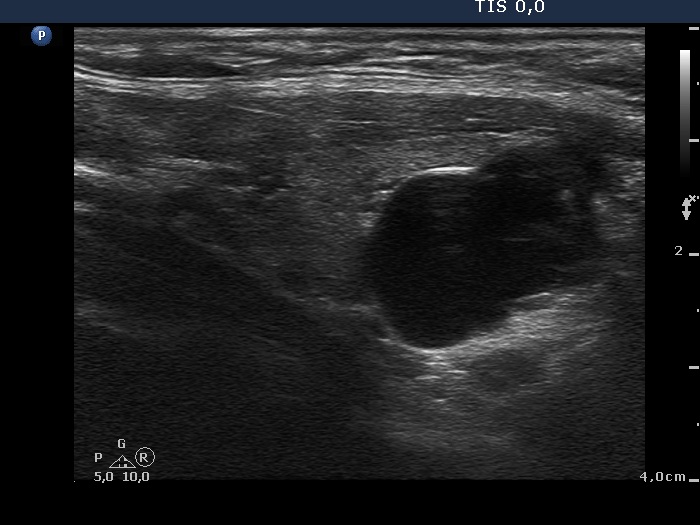

Ultrasonography: the thyroids were minimally-moderately hypoechogenic and presented fibrosis. There was a cystic lesion in the lower dorsal part of the right thyroid bed.

12 mL cystic fluid was aspirated. There were no cells on the smear.

Further laboratory tests aTPO 308 U/mL, calcium 2.25 mM/L, phosphorus 1.11 mM/L, parathormone 40.9 pg/mL (normal range: 10-65). The parathormone content of the cystic fluid was 383 pg/mL.